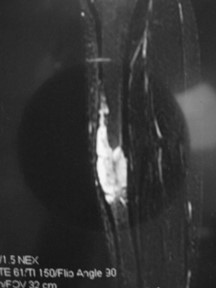

Radiographic Presentation

- Sharply defined osteolytic defect (lobulated, multicystic, or “soap bubble”)

- May be considerable perilesional sclerosis

- Cystic spaces and areas of intralesional hemorrhage are common